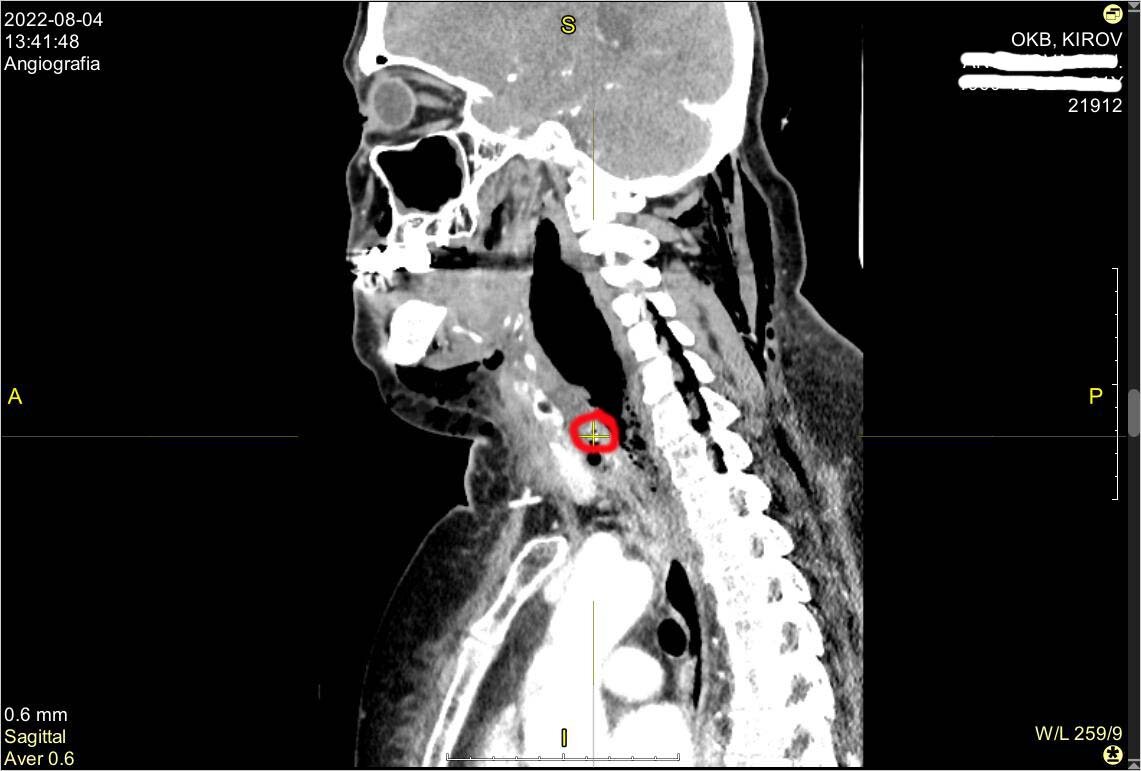

В областную больницу пациентка поступила в тяжёлом состоянии, вызванным сильнейшим обезвоживанием и интоксикацией. В результате компьютерной томографии специалистами было обнаружено инородное тело шейного отдела пищевода (рыбная кость) и флегмона шеи верхнего средостения. Ввиду того, что женщина поздно обратилась к врачам, гнойное воспаление тканей опустилось вниз, в полость между лёгким и сердцем, развилось чрезвычайно опасное для жизни инфекционное воспаление клетчатки средостения, причиной которого стала перфорация пищевода.